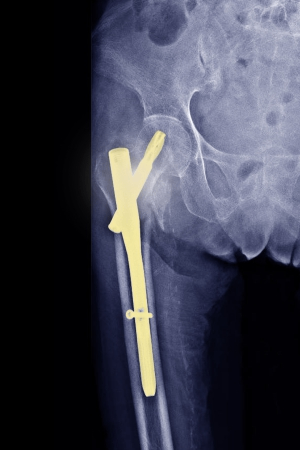

Hitting the Nail on the Head? Evolution of the cephalomedullary nail in the fixation of intertrochanteric hip fractures